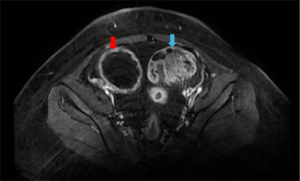

CASE LÂM SÀNG: ĐIỀU TRỊ MIỄN DỊCH BỆNH NHÂN UNG THƯ HẮC TỐ DI CĂN HẠCH, PHỔI TẠI TRUNG TÂM Y HỌC HẠT NHÂN VÀ UNG BƯỚU, BỆNH VIỆN BẠCH MAI. GS.TS Mai Trọng Khoa, BSNT. Mai Thị Quỳnh, PGS.TS Phạm Cẩm Phương, TS. Phạm Văn Thái, TS. Nguyễn Thanh...